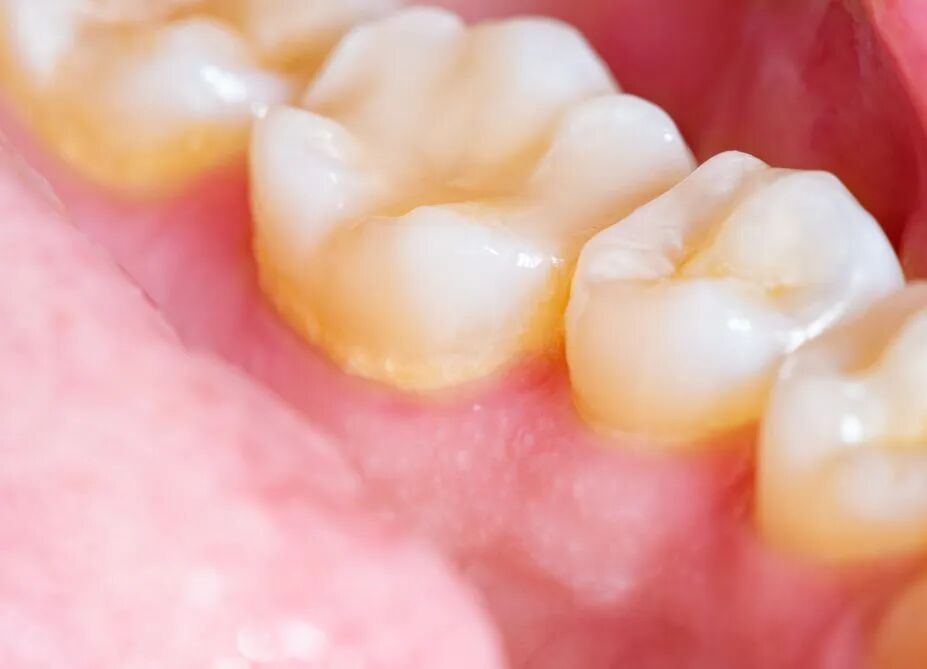

图为牙结石

图片来源:站酷海洛